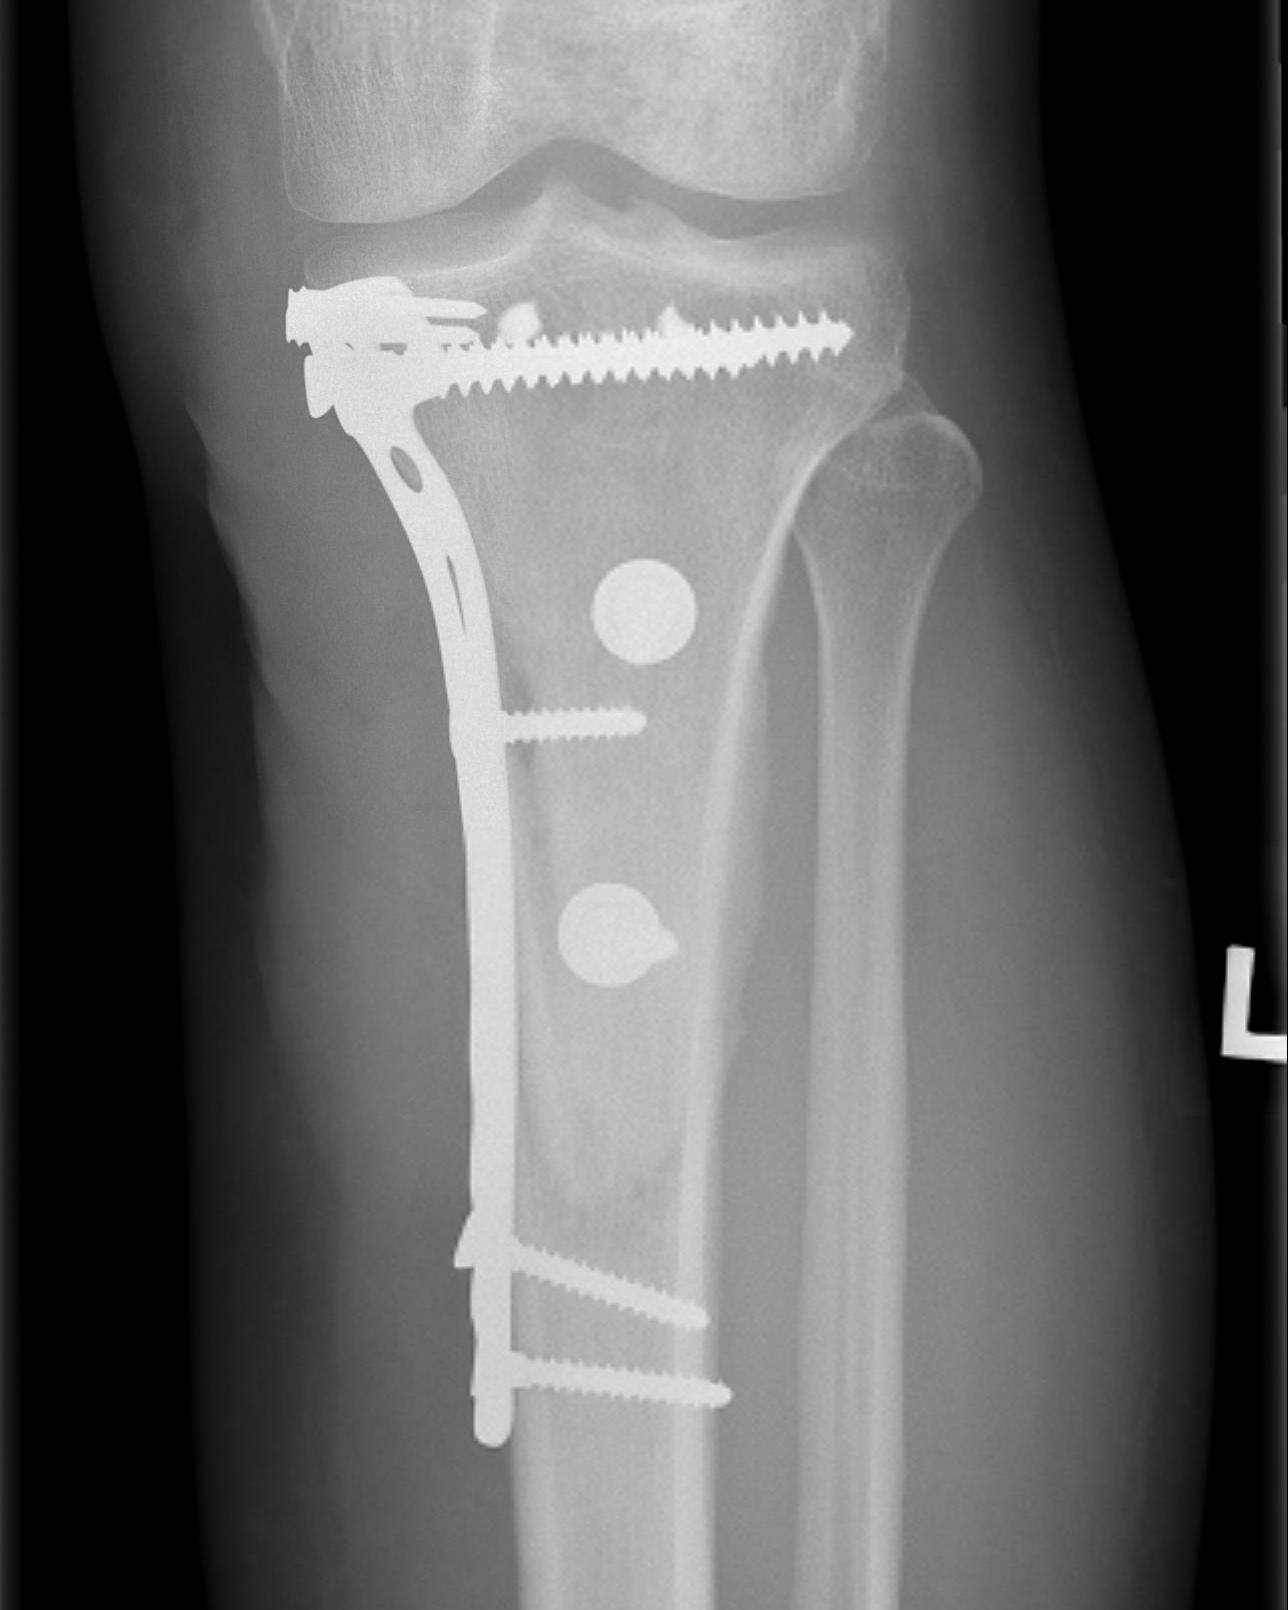

Parosteal Osteosarcoma distal femur

A. Hemicortical resection and posterior hemicortical allograft reconstruction

- hemicortical resection and hemicortical allograft reconstruction

- 22 cases (6 parosteal, 6 peripheral chondrosarcoma, 10 adamantinoma)

- all allografts incorporated